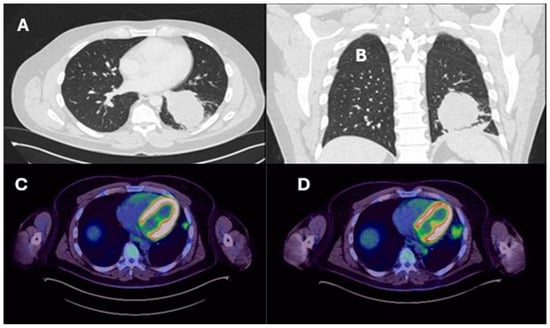

| Lung resection November 2022—Left lower lobectomy + lymph node dissection: pT3pN0 R0 resection. SMARCB1-deficient, PDL1-negative, TTF-1 negative, CD56-positive, cytokeratin positive. Pre-operative CT axial and coronal slices are shown in Figure 2A and Figure 2B, respectively. | Lung resection January 2022—right upper lobectomy + lymph node dissection: pT1cpN0 R0 resection. SMARCB1-deficient, PDL1 negative, TTF-1 negative, CD56-positive, cytokeratin-positive. Pre-operative axial PET slice shown in Figure 3A. |

| Recurrence December 2022—started 4 cycles of Gemcitabine/Cisplatin. Post-operative recurrence demonstrated in PET slices (Figure 2C,D) | Recurrence June 2022—progressive disease noted on CTPA (performed for SOB, pyrexia) at the right hilum, with soft tissue thickening at resection margins. Commenced on Pembrolizumab/Paclitaxel/Cisplatin with systemic intent. Recurrence shown in station 4R (Figure 3B), at the right hilum (Figure 3C) and in the right posterior bony skeleton in ribs 6–9 (Figure 3D). |